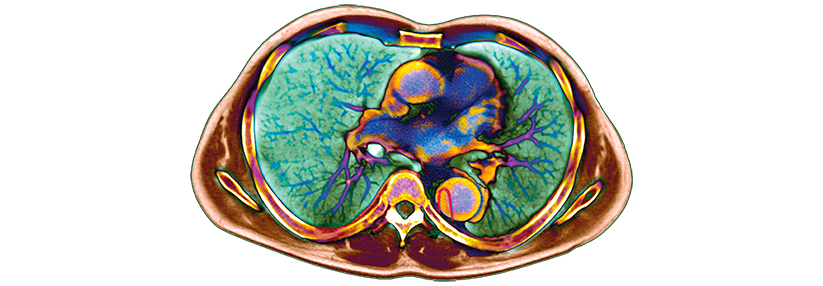

Diese 3D-Rekonstruktion aus der CT-Angiografie zeigt eine ausgedehnte Dissektion der thorakalen Aorta. Diese 3D-Rekonstruktion aus der CT-Angiografie zeigt eine ausgedehnte Dissektion der thorakalen Aorta. © Science Photo Library/Living Art Enterprises

Goldstandard in der bildgebenden Diagnostik sind Computertomografie und CT-Angiografie (CTA). Auch eine MRT-Untersuchung leistet gute ­Dienste.